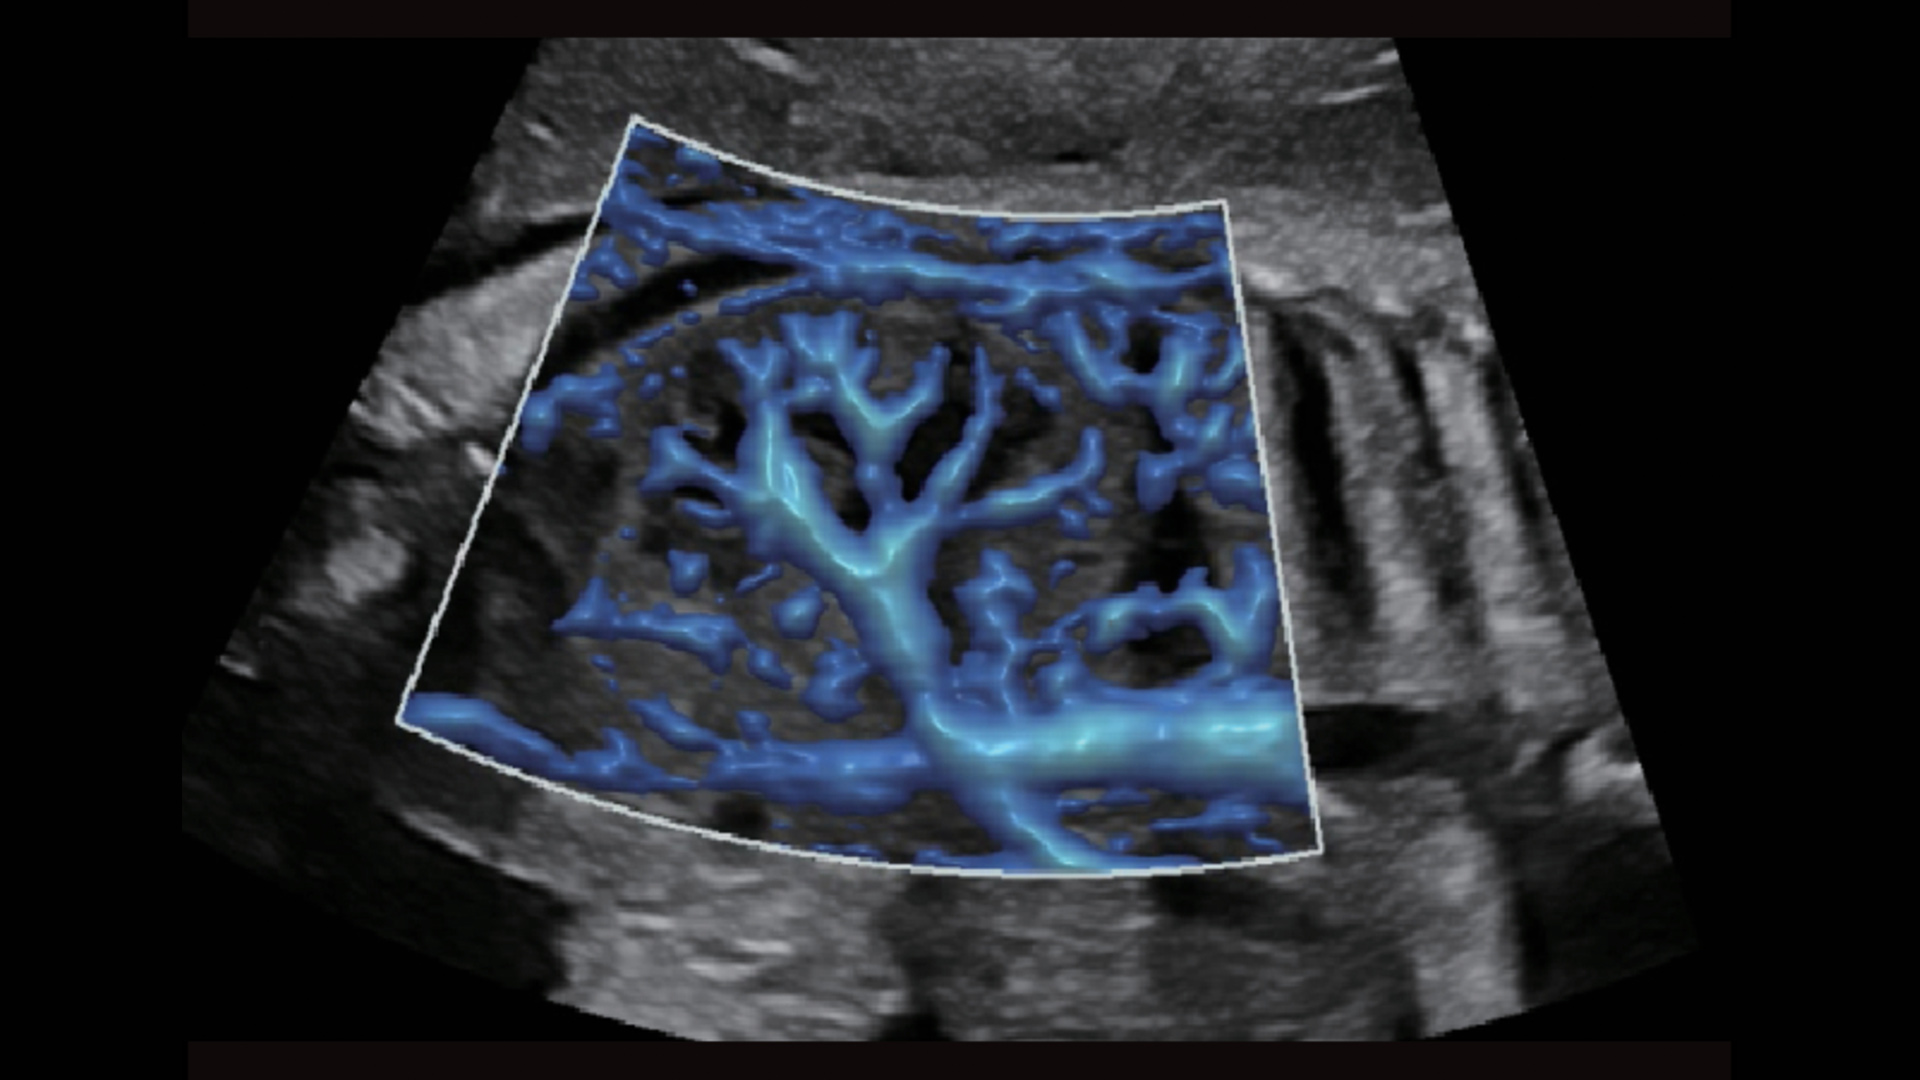

UMA (angiografia ultramicroscĆ³pica)

A tecnologia inovadora elimina as limita??es das tradicionais imagens com Doppler. Com resolu??o espacial e sensibilidade de fluxo ultra-altas, permite a detec??o de perfus?es de fluxos muito sutis e lentos, ampliando assim a aplica??o clĆnica da avalia??o qualitativa e quantitativa do ultrassom no cĆ©rebro fetal, rins, placentas, endomĆ©trios, ovĆ”rios etc.

UMA ā Fluxo renal do feto

UMA ā Fluxo uterino e endometrial